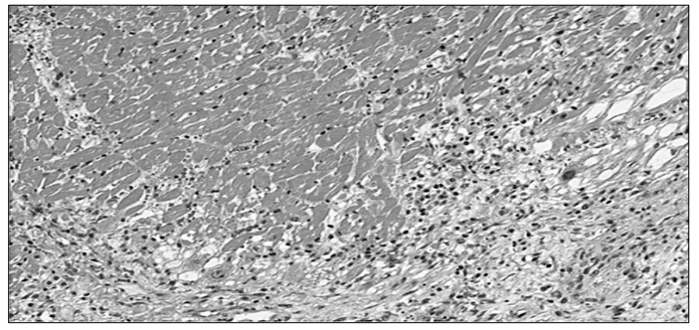

A imagem microscópica abaixo representa o corte histológico de uma lesão localizada na parede anterior do ventrículo esquerdo, encontrada no exame de necrópsia de um paciente de 48 anos de idade, sexo masculino, encontrado em óbito no seu domicílio:

Mediante as informações e a análise microscópica acima, assinale a alternativa correta.